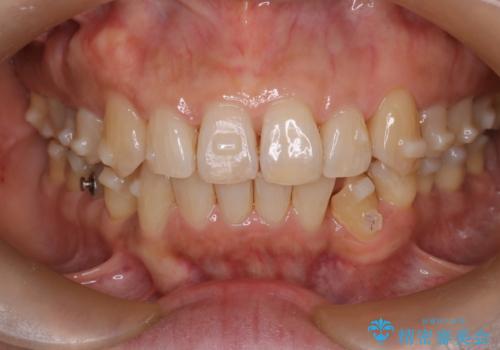

インビザラインで非抜歯矯正|ゴムかけで下顎犬歯の低位を改善し、噛み合わせも最適化

- 患者様は、下顎の犬歯が通常より低い位置にあり、噛み合わせのバランスが崩れていることを気にされて来院されました。診査の結果、抜歯せずに歯をきれいに並べるスペースを確保しながら、**ゴムかけ(顎間ゴム)**を使用して下顎犬歯の高さを適正に調整する方針を立てました。併せて、奥歯の噛み合わせも改善し、全体のバランスを整えることを目標としました。

治療はインビザライン(マウスピース矯正)を使用し、歯列全体を計画的に移動させながら、下顎犬歯の低位をゴムかけによって徐々に引き上げました。患者様にはゴムの装着をしっかり継続していただき、順調に改善が進行。最終的に奥歯の噛み合わせも安定し、全体の咬合バランスが整いました。治療後は「自然な噛み心地になり、見た目も満足」と患者様にも喜んでいただきました。